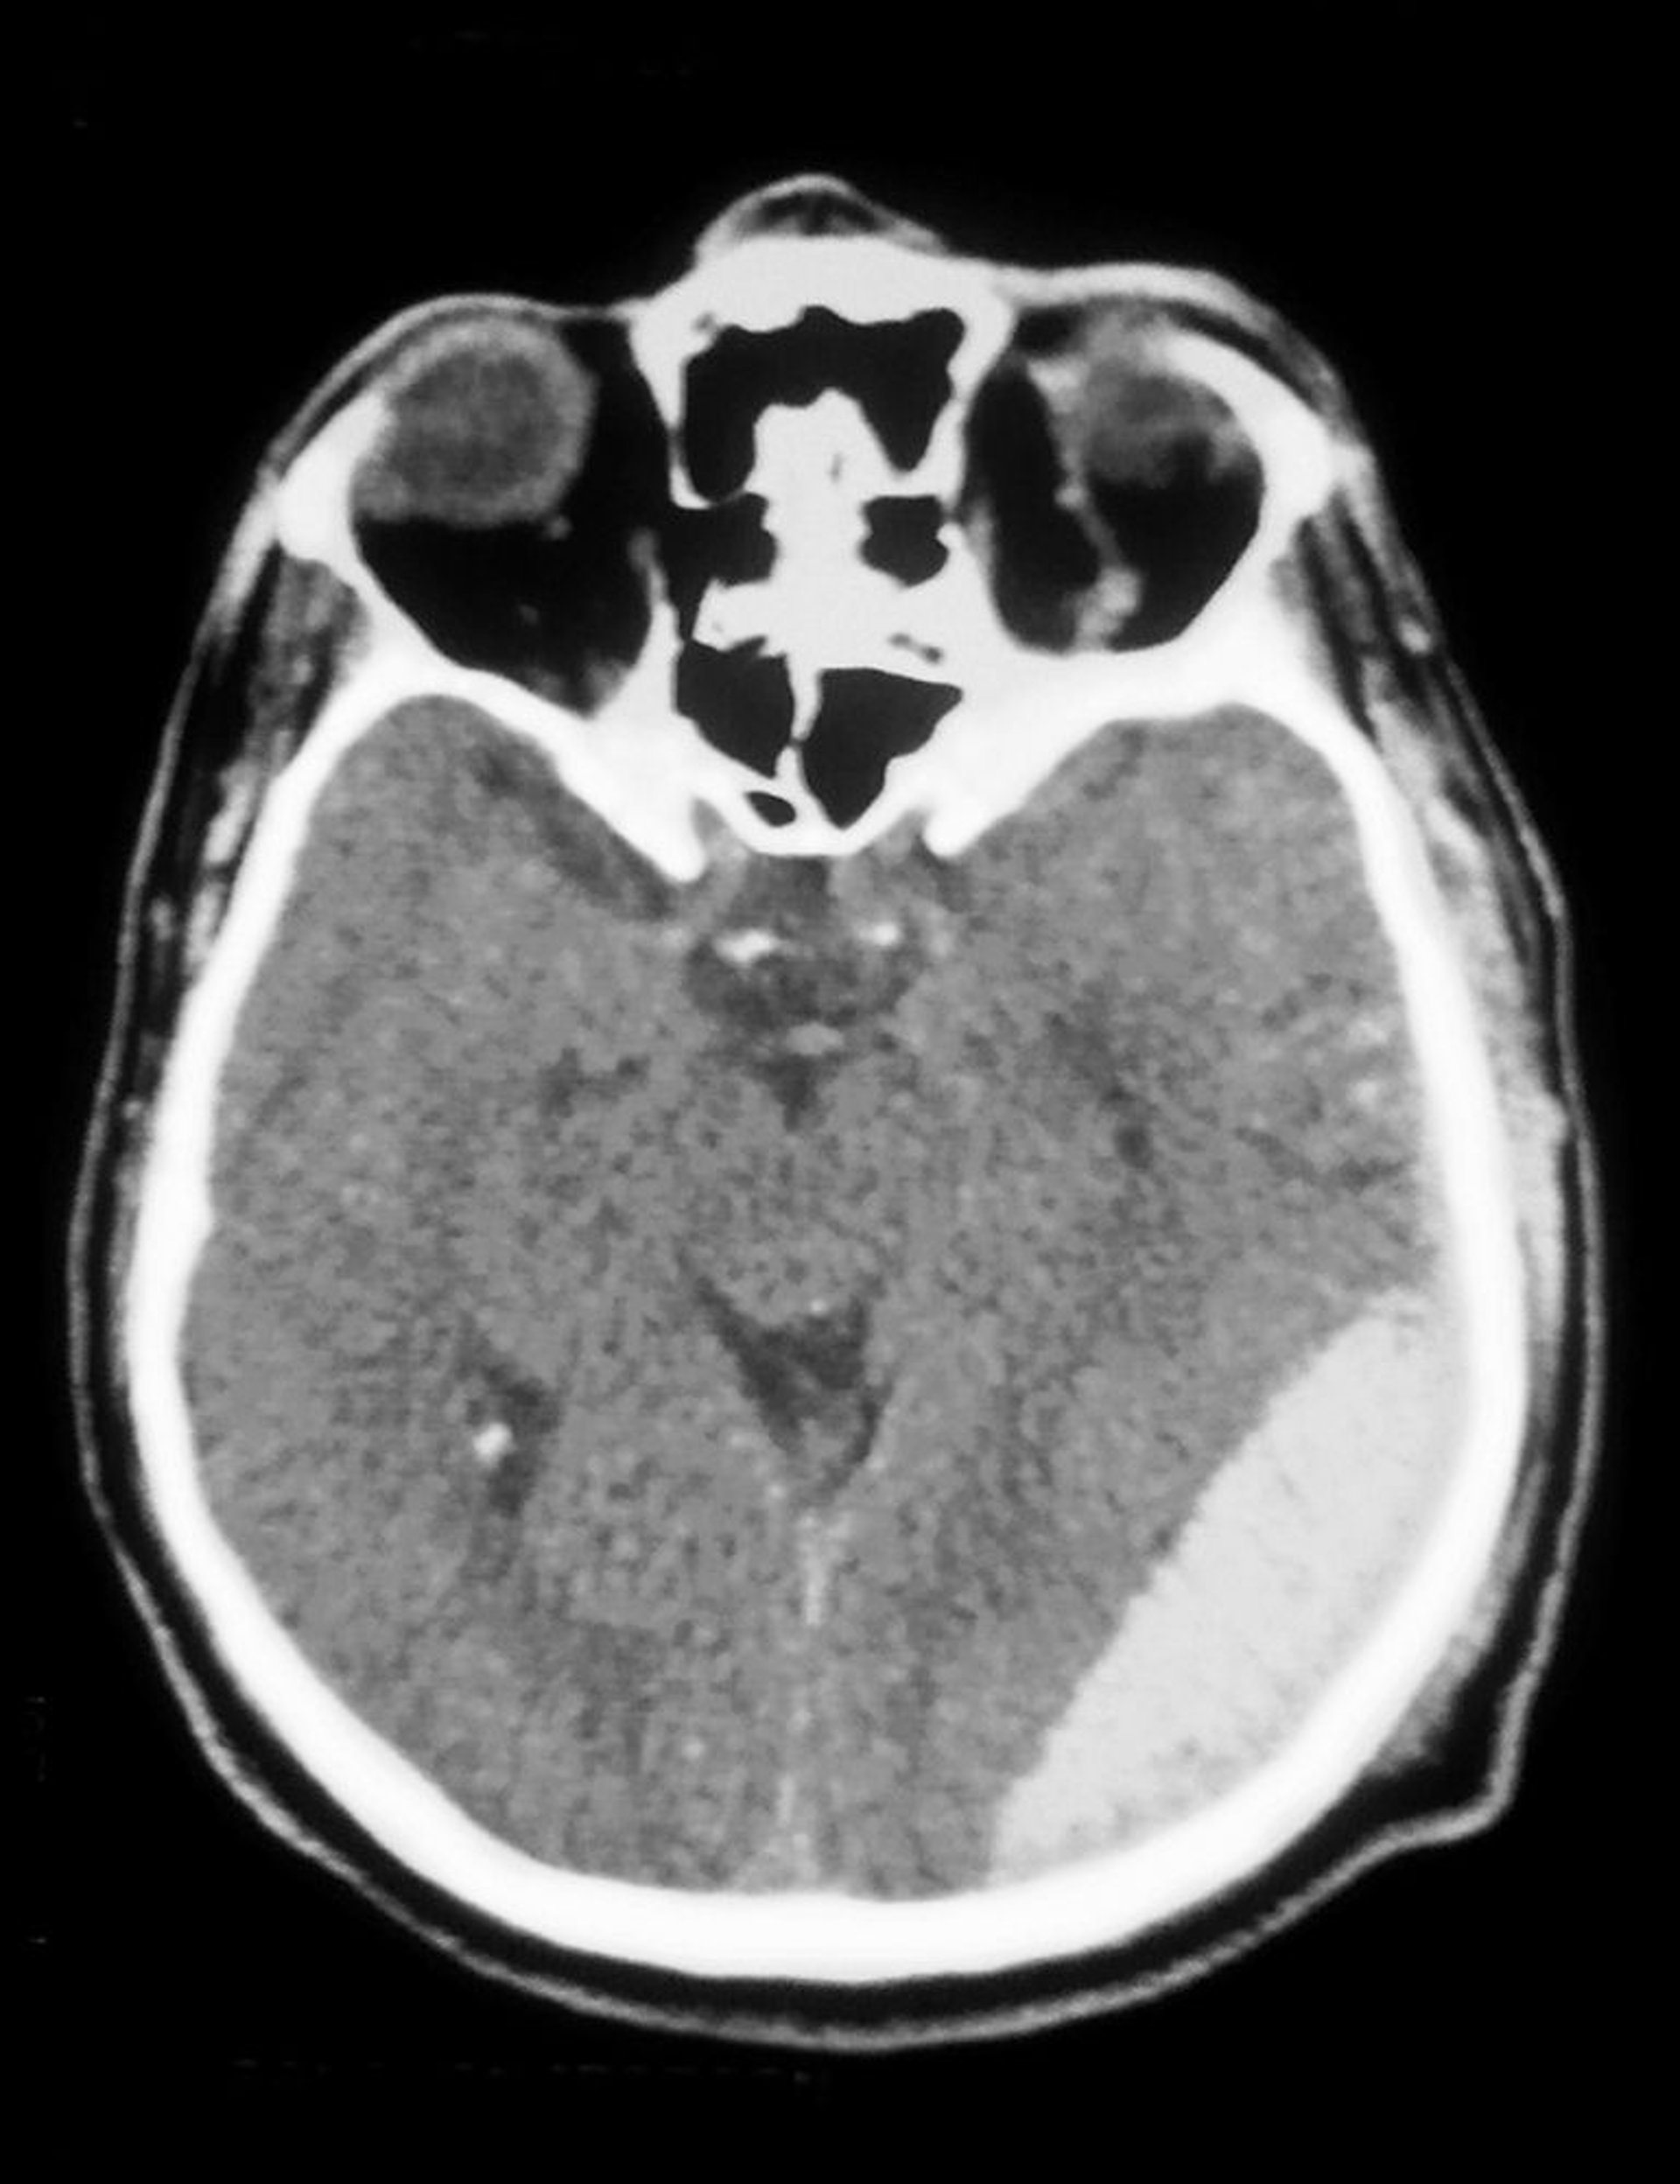

Эпидуральная гематома

На КТ видна эпидуральная гематома (затемнение внизу справа).